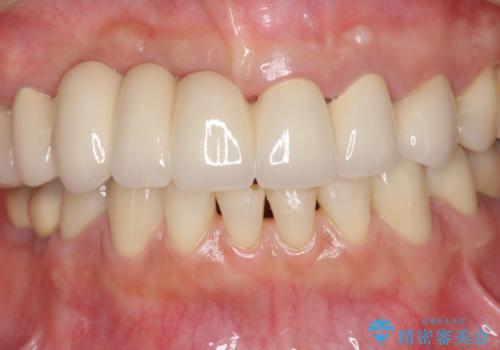

咬合性外傷による歯槽骨吸収 ブリッジ補綴

- 歯が揺れしっかりとものが噛めないことの改善を求めて来院されました。

保存の難しい歯の抜歯、保存できる歯の歯周病治療、欠損部位の歯槽堤形態回復を含めブリッジによる安定した咬合機能回復を計画します。

- 90万円 (仮歯×9 メタルボンドクラウン×9)費用は治療当時の料金となります

ブリッジは欠損した部位に臨在する歯を削り、被せなければいけないというデメリットがありますが反面噛む力が強い場合連結することで強大な咬合力に対抗できるというメリットも存在します。